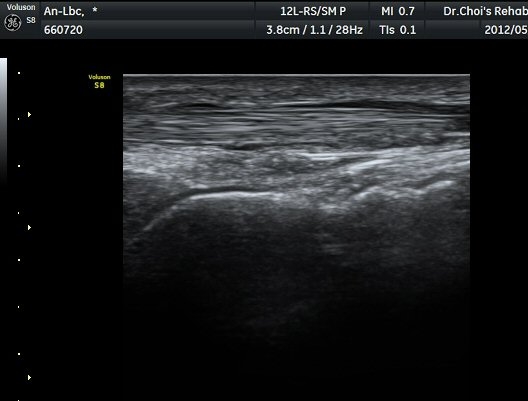

¹ß¸ñ ¾Õ Ⱦ´Ü¸é°Ë»ç¿¡¼­ Àü°æ°Ç(TA), ¾öÁö½ÅÀü°Ç(EPL), ¹ß°¡¶ô½ÅÀü°Ç(EDL)ÀÇ ºÎÁ¾ ¹×

°Ç ÁÖÀ§ ¼ö¾× Àú·ù°¡ °üÂûµÈ´Ù(»çÁø 1, 2). °ÇÀÇ ºñÈÄ¿Í ¼ö¾×Àú·ù´Â °ÇÃø(»çÁø 4)°ú ºñ±³Çϸé

¶Ñ·ÈÇÏ´Ù. Àü°æ°Ç Á¾´Ü¸é°Ë»ç¿¡¼­ °ÇÀÇ ºÎÁ¾°ú °Ç ÁÖÀ§ ¼ö¾× Àú·ù°¡ °üÂûµÈ´Ù(»çÁø 3). °ÇÀÇ

ºÎÁ¾°ú ¼ö¾×Àú·ù´Â °ÇÃø°ú ºñ±³ÇÏ¸é ¶Ñ·ÈÇÏ´Ù(»çÁø 5).¤·